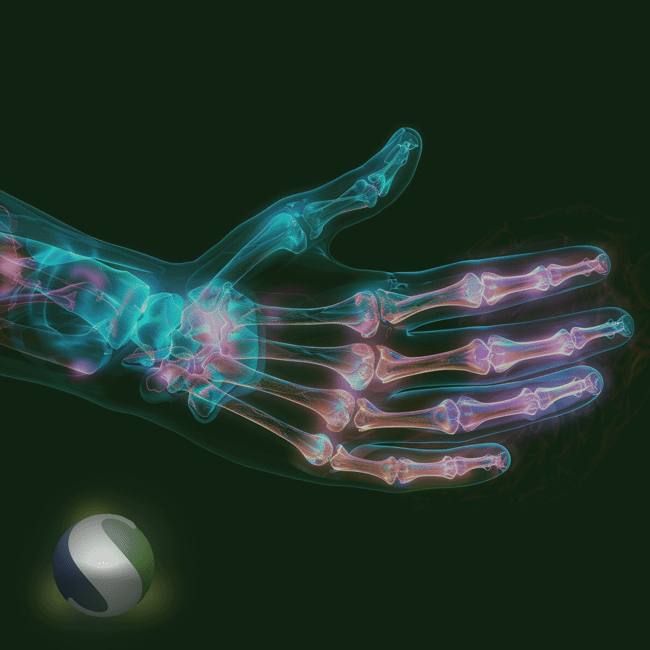

TRAUMATOLOGIA

Trabalhamos com marcas reconhecidas e comprometidas com a inovação, qualidade e segurança, assegurando produtos que atendem aos mais rigorosos padrões técnicos. Nossa missão é contribuir com o trabalho dos especialistas, promovendo o melhor resultado clínico e a rápida recuperação dos pacientes. Conte com um portfólio completo e eficiente, pensado para atender às necessidades do dia a dia hospitalar com precisão e confiança.